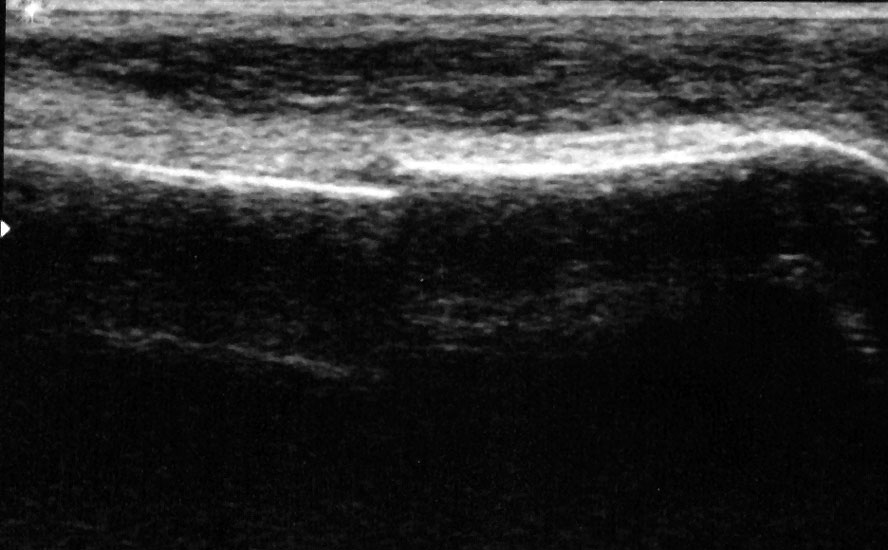

Ruptur Lig. fibulocalcaneare

Längsschnitt über dem Lig. fibulocalcaneare. Die Peronealsehnen erscheinen als echoreiche runde bis ovaläre Struktur.

Abbildung 19

Lagerung: Rückenlage, OSG in Neutralstellung.

Schnittebene: LS über Lig. fibulocalcaneare.

Referenzstrukturen: Fibulaspitze und Talus.

Befunde: Das Lig. fibulocalcaneare is nativ schlecht abgrenzbar, da es in die Tiefe und nicht parallel zum Schallkopf verläuft. Direkt über das Band ziehen quer getroffen die Peronäussehnen. Durch die Distorsion kann auch das Peritendineum peroneale einreißen. Die Peronealsehnen sind dann in ihrer Sehnenscheide von Blut umgeben, was sich als echoarmer Ring (Halo-Phänomen) darstellt und ein indirektes Zeichen für eine Verletzung des Lig. fibulocalcaneare ist.